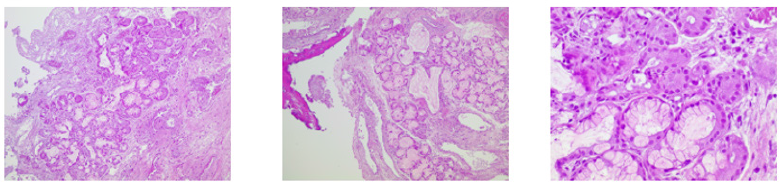

The lesion of the clivus was excised and an endonasal endoscopic closure of the dural defect was performed through the fascia lata, fat, and Hadad flap. 3 days after discharge, she presented an emetic event with a new episode of CSF rhinorrhea. An emergency repair of the fistula was successfully conducted. Finally, the histological results revealed salivary gland heterotopia [7-13] (Figures 1-3).

Salivary gland heterotopia in the clivus is a rare entity (salivary gland tumors represent almost 3% of all tumors of head and neck) with a casual diagnosis that was secondary to a CSF fistula after a nasal swab, which is in itself a rare condition. Salivary gland heterotopia must be treated with surgery, not only because of the CSF fistula in this case, but in general terms because this lesion risks becoming a pleomorphic adenoma.